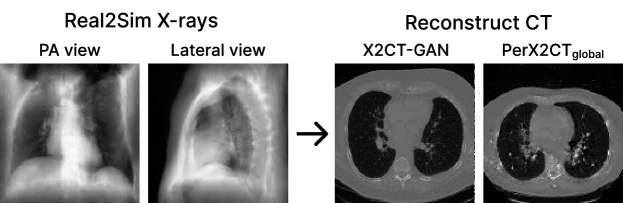

Refer to caption

Figure 5: Qualitative results of the real X-ray projection.

3.4 Real-world Experiment

To obtain an X-ray pair (PA and Lateral) and a CT scan that were taken exactly at the same time is hardly happens in reality. Therefore, we trained Real2Sim CycleGAN [28] using 500 synthetic and real X-rays randomly selected from our training set and MIMIC-CXR [29]The MIMIC-CXR-JPG data were available on the project website at https://www.physionet.org/content/mimic-cxr-jpg/2.0.0/, respectively. After that, we translated real X-rays by CycleGAN and used them as input of our model. Because there is no ground-truth CT corresponding to the X-ray, it is impossible to evaluate accurately. Instead, we provide qualitative results in Figure 5. As shown in Figure 5, PerX2CT provides a clearer boundary than in X2CT-GAN, even in a real-world setting.